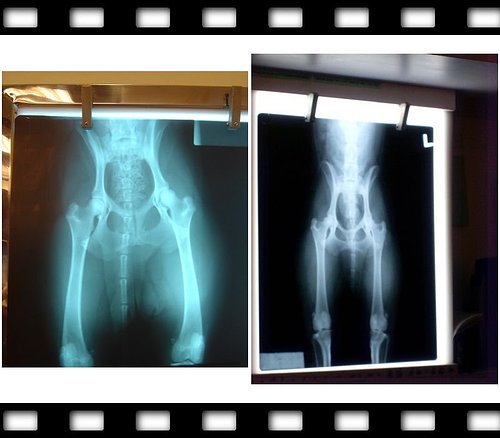

左圖的就是妮卡六個月結紮的時候,脊椎不正、雙腳沒拉直失敗

右圖是今天照的,山海媽說左腳包覆超過2/3 健康寶寶一枚、右腳也超過1/2很不錯

(左腳角度107、右腳106皆正常)

醫生也說妮卡骨骼很棒也很健壯,骨架也很大,所以22.5KG算正常